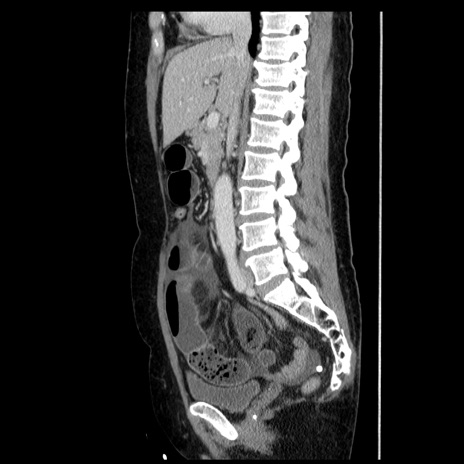

症例6(矢状断像)

【症例】50歳代女性

【主訴】下腹部痛

【現病歴】本日朝より下痢2回あり。 昼食を食べた後、嘔吐3回、下腹部痛認め、症状軽快せず、当院救急搬送。

最終食事:本日昼(生ものなし)。 昨日の夜、刺身を食ぺたとのこと。周囲に同様の症状の者なし。普段、排便は毎日あるとのこと。

【既往歴】卵巣癌術後(8年前に当院で卵巣摘出)

【身体所見】 意識清明、腹部:平坦、腸蠕動音→、やや硬、下腹部自発痛・圧痛あり、反跳痛あり、筋性防御なし。

【データ】WBC 16000、CRP 0.01